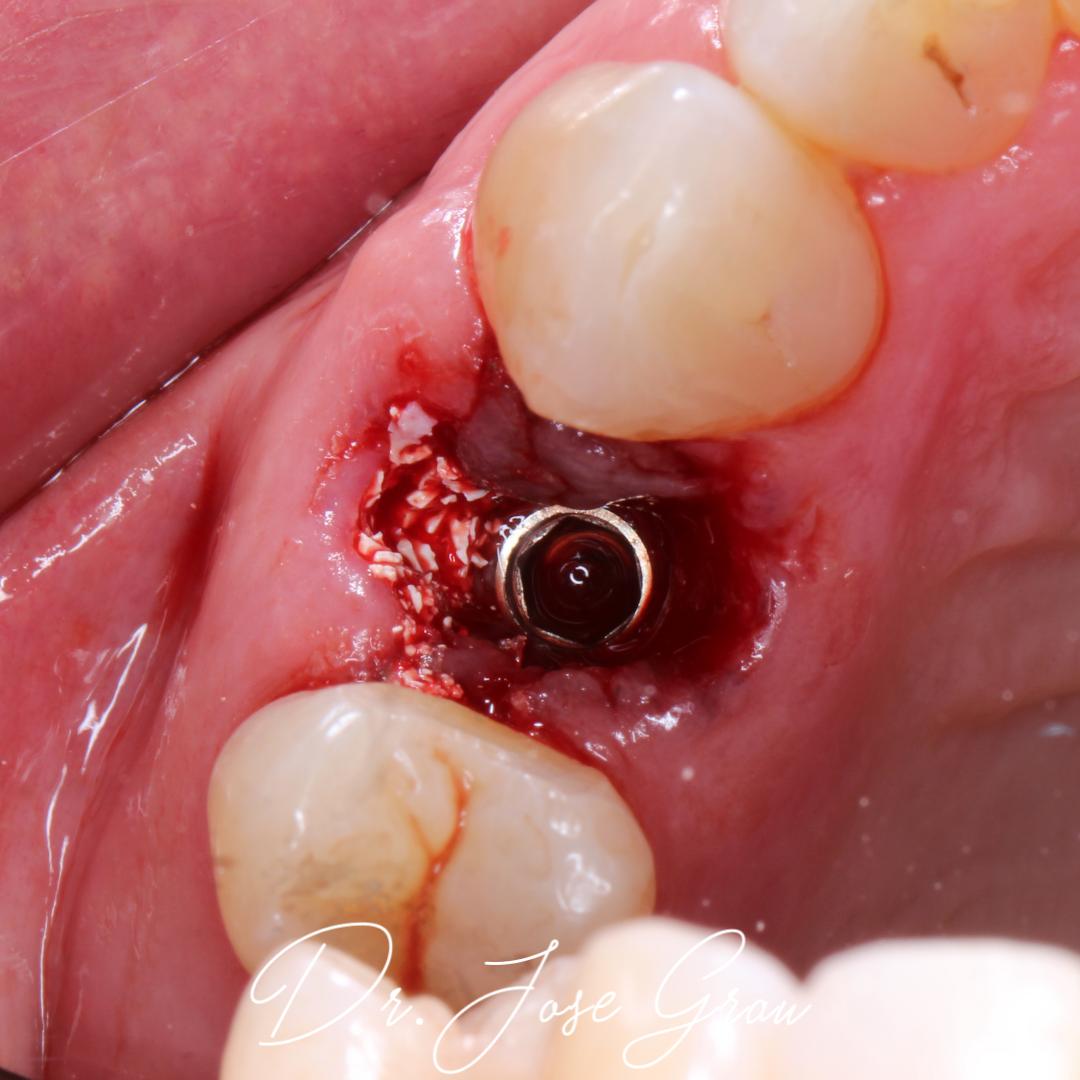

Implante inmediato con carga inmediata